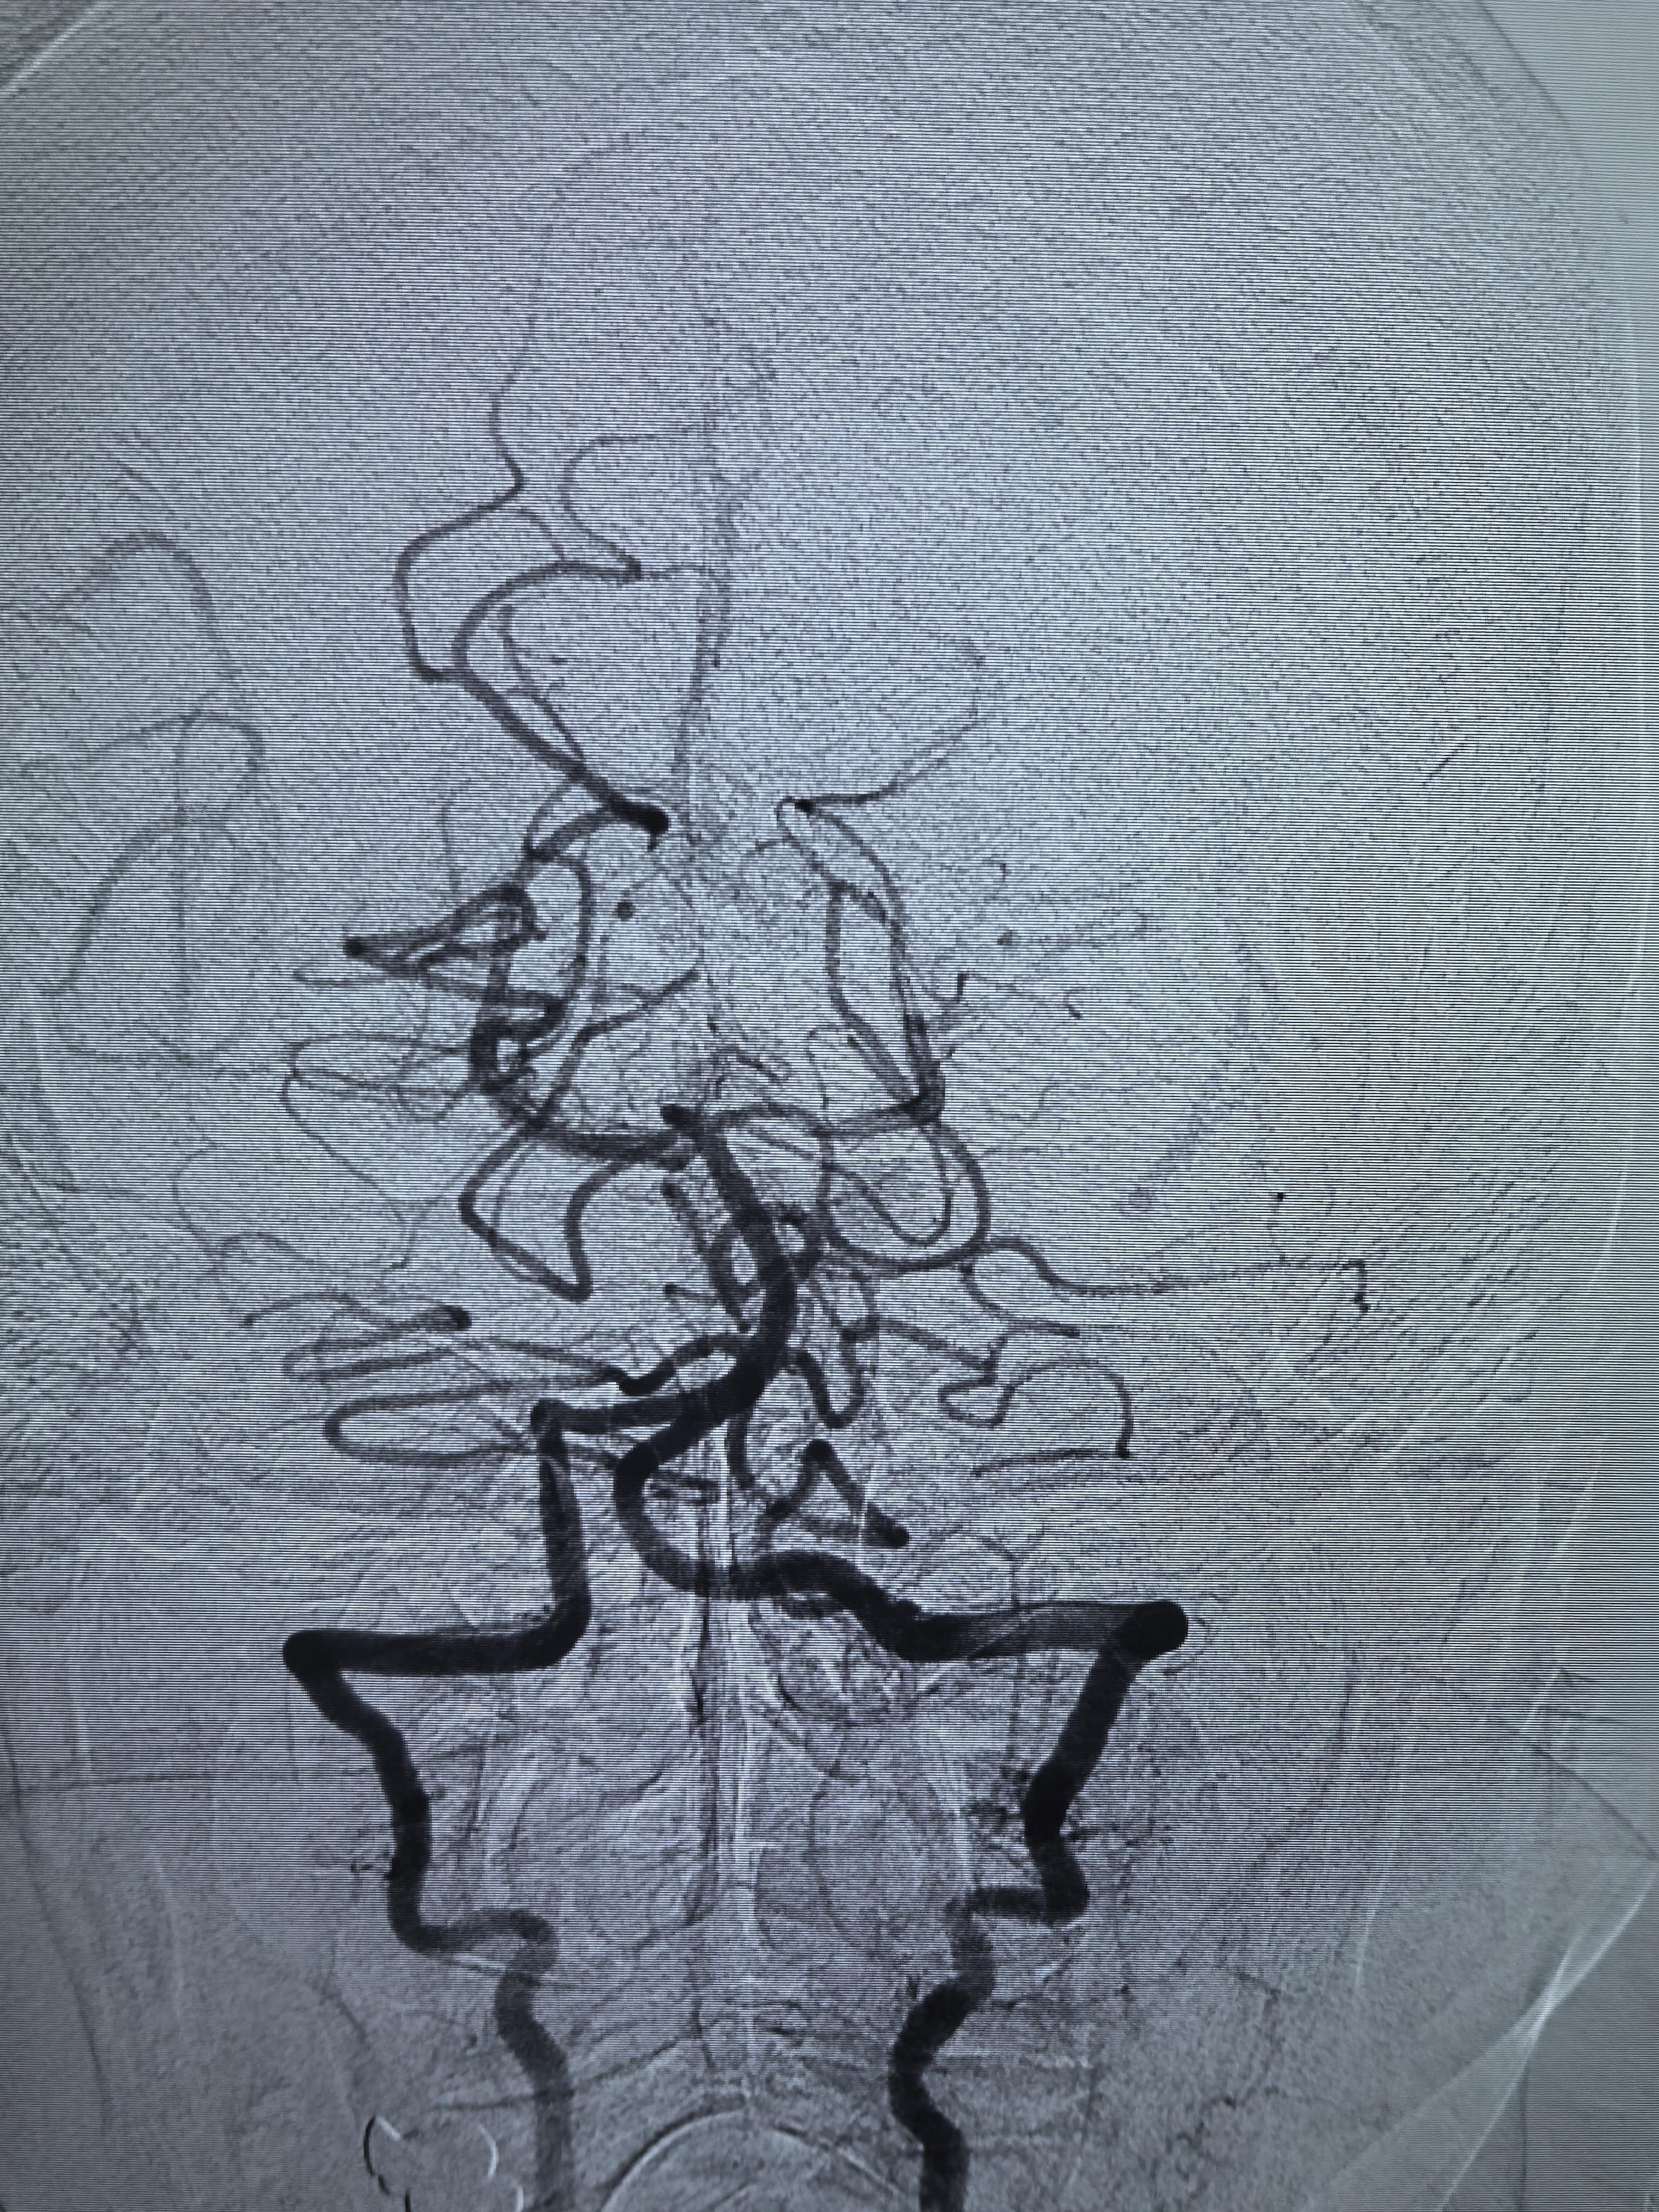

支架导管栓塞导管到位!

动脉瘤栓塞满意,胚胎型大脑后动脉还有血流通过,栓塞致密程度还不够,考虑破裂动脉瘤,先降低出血风险,动脉瘤大,大小约12.6*8.5mm,复发风险高,将来复发再考虑血流导向植入!

术后侧位造影,后交通动脉血流还是减少!

术后正位造影!

术后椎动脉造影左侧大脑后动脉显影良好!

蒙片看支架及弹簧圈!支架打开良好!